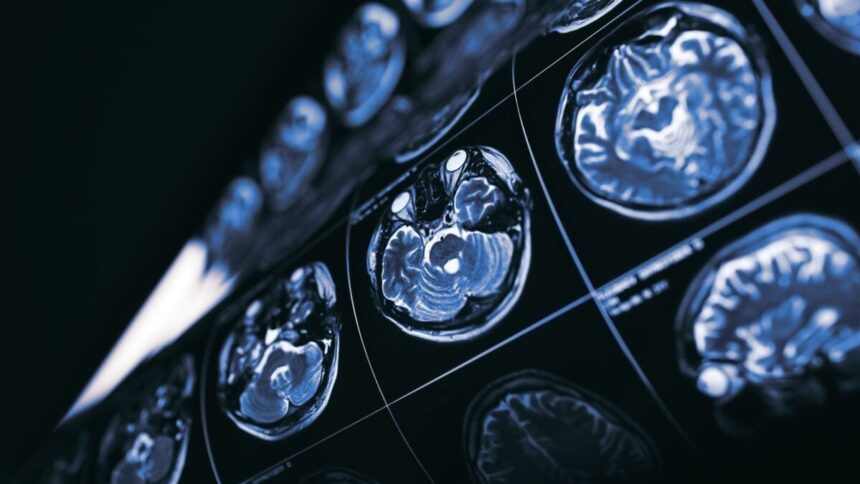

The brains of people with Alzheimer’s become cluttered with the misfolded forms of two proteins, amyloid beta and tau. Some research has suggested that amyloid beta in particular drives the brain’s destruction in Alzheimer’s. And that’s led scientists to develop antibody-based drugs that try to eliminate amyloid from the brain, hoping to slow or even reverse Alzheimer’s symptoms.

At the same time, these drugs are known to cause something known as amyloid-related imaging abnormalities, or ARIAs, which are markers of swelling or bleeding of the brain. Though ARIAs can be a serious issue, the review did not find evidence that anti-amyloid drugs increase the risk of death compared to placebo. Still, the verdict in general is plenty gloomy.